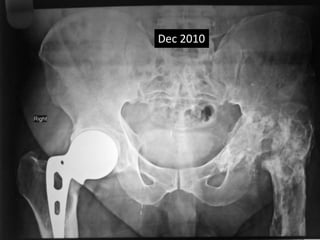

• 36 yrs Male

• AMP done 1988 rt side at the age of 36 yrs

• THR cemented done on left 1990 at the age of 38.

• Metal fatigue 2012

• Last follow up Nov 2014.

Dec 2010

Incidental finding

Signs of metal fatigue

2012

Nov 2014

No pain

Not aware of broken prosthesis

AMP

1988 - 2014